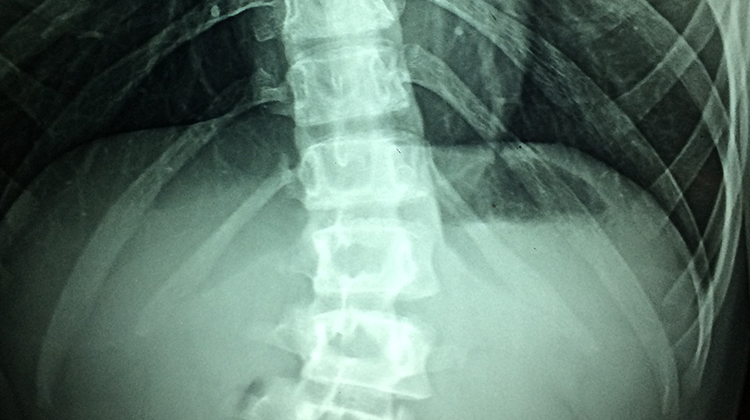

X-ray 검사

허리디스크 질환설명

허리디스크는 요추(허리)의 뼈와 뼈 사이의 추간판이 탈출하거나 파열되어 요추(허리) 신경이 압박을 받아 허리에 통증이 일어나는 질환입니다.

‘디스크(추간판)’는 원래 척추의 뼈와 뼈 사이에 있는 편평한 판 모양의 물렁뼈를 가리키는 말입니다.

디스크의 외부는 섬유륜이라는 막으로, 내부는 젤라틴처럼 탄력이 있고 점성을 띠는 반액체인 수핵으로 구성되어 있습니다.

이 외부의 섬유륜이 외상이나 퇴행성 변화 등에 의해 찢어지거나 파열되면 내부의 수핵이 밖으로 밀려 나와 주위 조직, 특히 척추 신경을 압박하면서 통증 등의 증상을 유발합니다. 이것을 ‘디스크’, 또는 ‘추간판탈출증’이라고 합니다.

각각의 척추신경은 고유한 영역의 감각과 운동을 담당하기 때문에 디스크가 발생한 위치에 따라 통증의 위치와 양상이 달라집니다.

허리디스크의 경우 제4번과 제5번 요추(허리뼈) 사이, 제5번 요추와 제1번 천추(엉치뼈) 사이에서 주로 발생하는데, 예를 들어 탈출된 디스크가 다섯 번째 요추신경을 압박하면 종아리 바깥쪽이나 발등, 발바닥 등에 통증이나 저린 감각을 느끼게 됩니다.